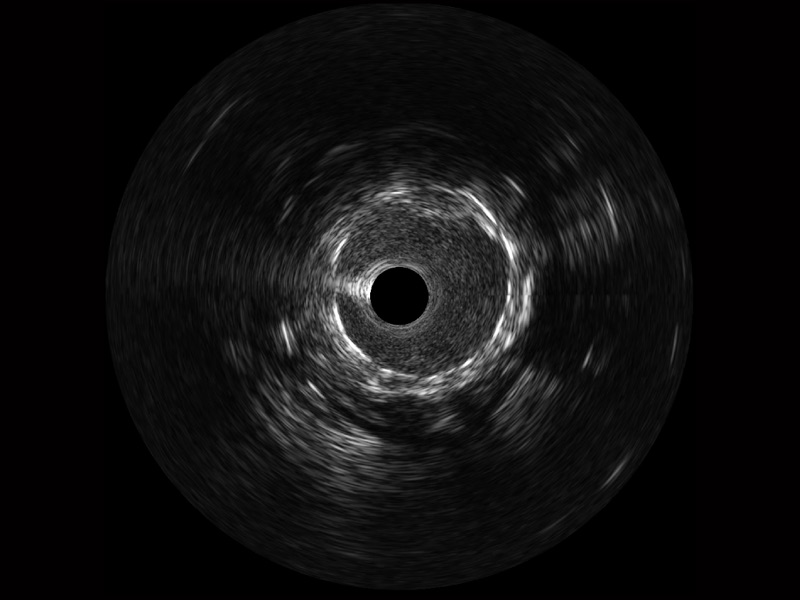

传统IVUS图像

对比传统IVUS导管成像,百老汇电子游戏官网宽频IVUS图像的近场支架梁显影更细腻,远场中膜外血管仍清晰可辨,兼顾远中近,兼顾分辨力与穿透深度